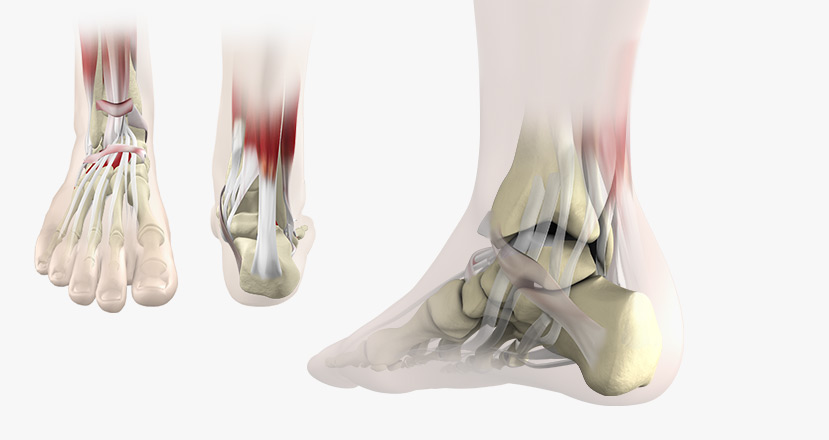

Foot-Ankle